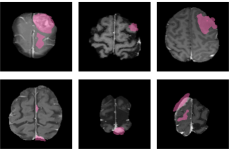

The visual results in Figure 6 show that GBT-SAM produces segmentations that align closely with the ground-truth annotations across all four studied brain tumor domains. The overlap (purple regions) highlights the ability of the model to accurately delineate tumor boundaries and extension. However, there are minor inaccuracies in certain pixels where the model slightly over- or under-segments the tumor regions, particularly in more complex cases or regions with low contrast. These results reflect the robustness of the method in generalizing across different tumor types while acknowledging potential refinement in future work.

Refer to caption

Figure 6: Visual comparison of ground-truth (pink) and our predictions (blue). The purple regions represent the overlap between the ground-truth and our predictions. Each column shows two examples per domain, demonstrating that the predicted segmentations closely match the annotations across diverse cases.